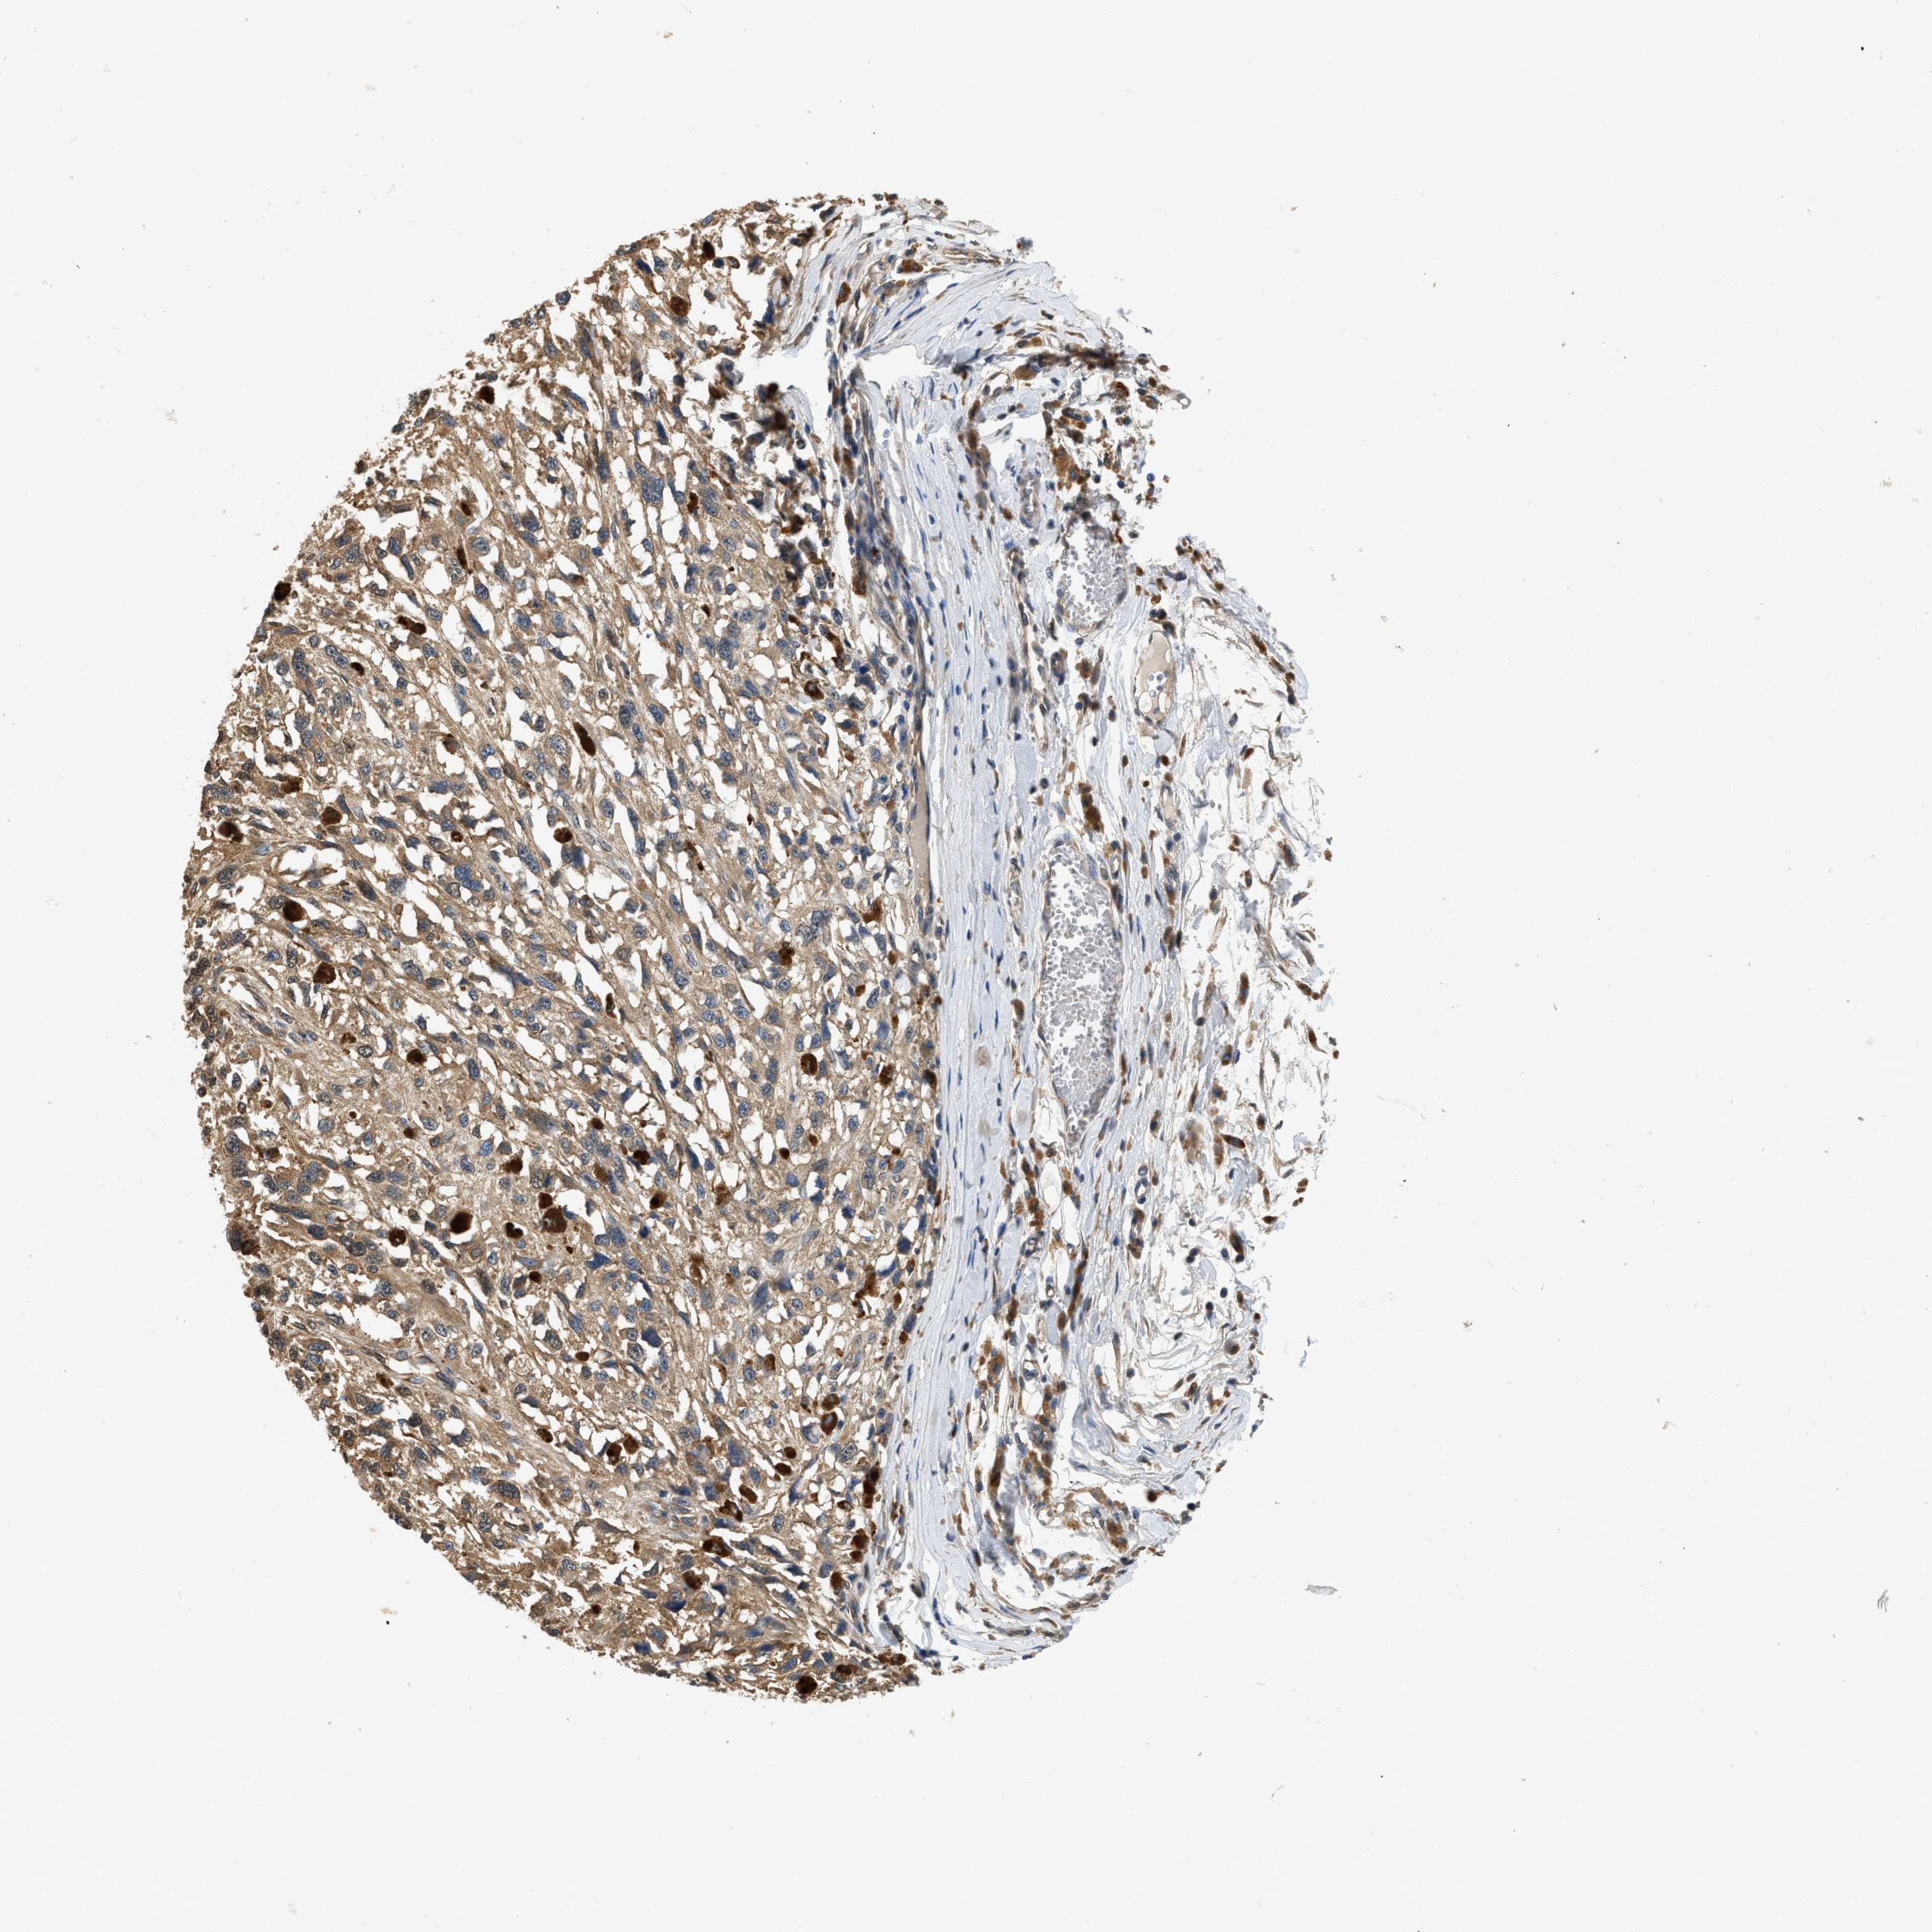

MELANOMA - Protein expressioni

A mouse-over function shows sample information and annotation data. Click on an image to view it in a full screen mode. Samples can be filtered based on level of antibody staining by selecting one or several of the following categories: high, medium, low and not detected. The assay and annotation is described here.

Note that samples used for immunohistochemistry by the Human Protein Atlas do not correspond to samples in the TCGA dataset.

Antibody stainingi

Antibody staining in the annotated cell types in the current human tissue is reported as not detected, low, medium, or high, based on conventional immunohistochemistry profiling in selected tissues. This score is based on the combination of the staining intensity and fraction of stained cells.

Each image is clickable and will lead to virtual microscopy that enables deeper exploration of all samples and also displays staining intensity scores, fraction scores and subcellular localization as well as patient and tissue information for each sample.

Antibody HPA018676

Staining

High

Medium

Low

Not detected

Intensity

Strong

Moderate

Weak

Negative

Quantity

>75%

75%-25%

<25%

None

Location

Nuclear

Cytoplasmic/membranous

Cytoplasmic/membranous,nuclear

Malignant melanoma, NOS

Malignant melanoma, Metastatic site